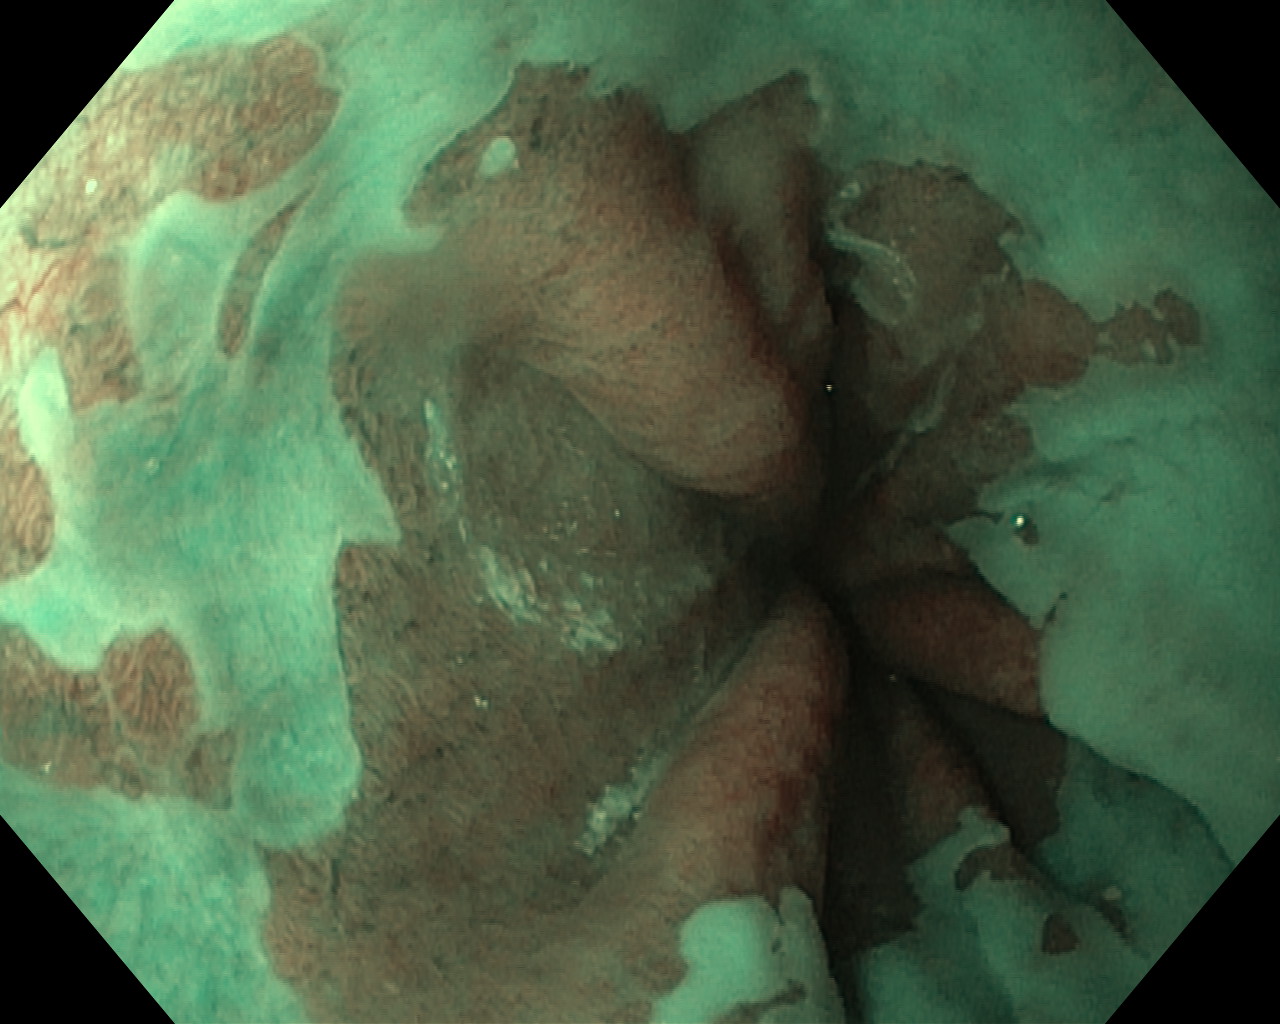

Przełyk Barretta